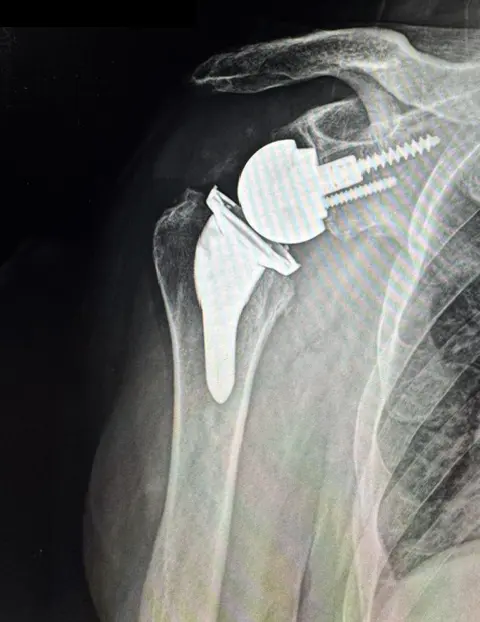

X-ray of a reverse shoulder replacement from Dr. Woodhead in Lincoln, NE

Reverse Shoulder Replacement

Reverse shoulder replacement is a surgical procedure that reconfigures the shoulder’s joint by reversing ball and socket orientation and altering the joint’s anatomical structure.